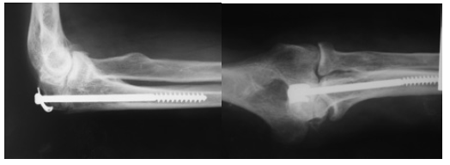

Материал и методы. С 2009г. по 2012г. в нашей клинике применялся остеосинтез длинным губчатым компрессирующим винтом. Было про-ведено ретроспективное сравнение результатов такого лечения с более традиционными методами фиксации (спицы, спицы с экстензионной петлей и т.д.), которые применялись в НЦТО с 2001г по 2009г., и консервативным методом лечения. Были применены клинические, рентгенологические и антропометрические методы обследования. Изучены результаты лечения 90 больных с переломами локтевого отростка, из которых 71 (78,9%)-изолированные переломы локтевого отростка, а в 19(21,1%) случаях перелом локтевого отростка сопровождался переломами других костей, образующих локтевой сустав, или вывихами костей предплечья. 17(18,8%) лечились консервативно, у 4(4.4%) было произведено параоссальное ушивание лавсаном, у 39(43,3%) была применена экстен- зионная петля на спицах (рис.1), и у 8(8,9%) фик-сация была произведена спицами без петли.